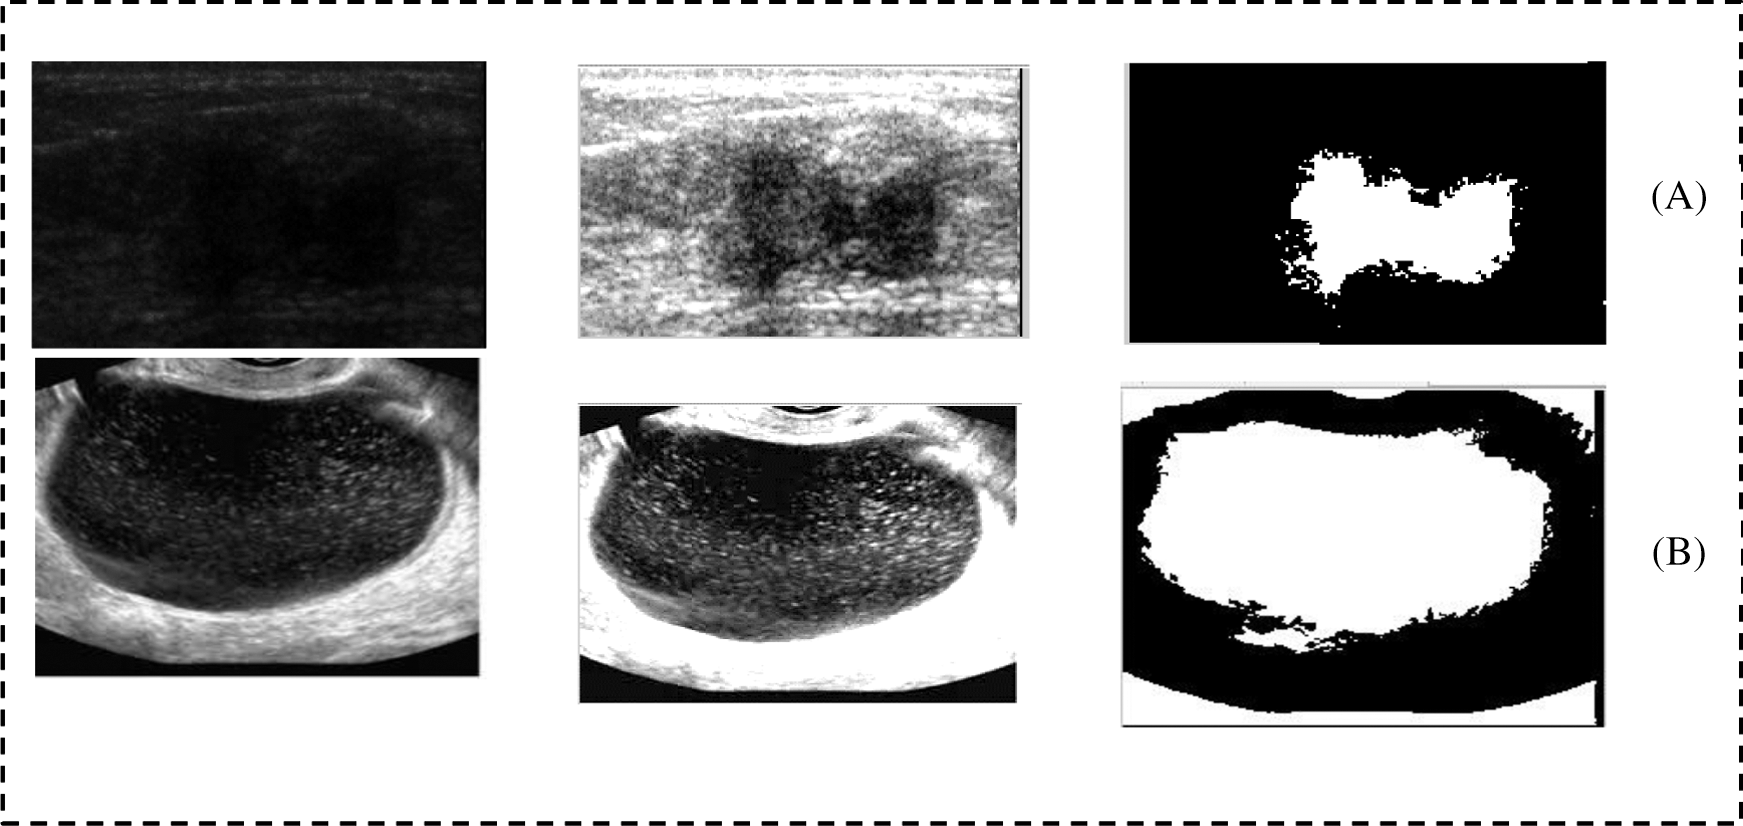

The execution of the proposed segmentation was also compared with the current methods utilized to segment diverse types of US cases see Tab. 1. We used previous studies as bases to determine that these techniques are well-known and efficient for distinctive types of US cases. Evidently, the proposed mode achieved good results compared with Otsu’s method and that with active contour. To see the affective of the proposed model we have shown the result of the prepressing as well as segmentation in Fig. 9. Fig. 9 shows that pre-processing enabled us to highlight ROI and reduce the artifacts. The proposed segmentation captured ROI from the remainder of the images.

Figure 9: Shows the preprocessing and segmentation of six cases taken from the breast and ovarian ultrasound images; (A and B) shows the breast cancer cases; (D and E) shows the ovarian tumor cases

Fig. 10 shows two samples of images that taken from the data set. Those images has more challenges and as we can see that border of those images is not clear and that has made the images more difficulties. Therefore, we have applied the proposed method to highlight the border of the ROI and make the ROI more clear. Then we applied the segmentation method to extract the ROI as a binary object. We can see that the proposed method has extract the ROI without under and over-segmentation problem.

Figure 10: Two samples from the breast and ovarian cases. (A) Breast case and (B) Ovarian case